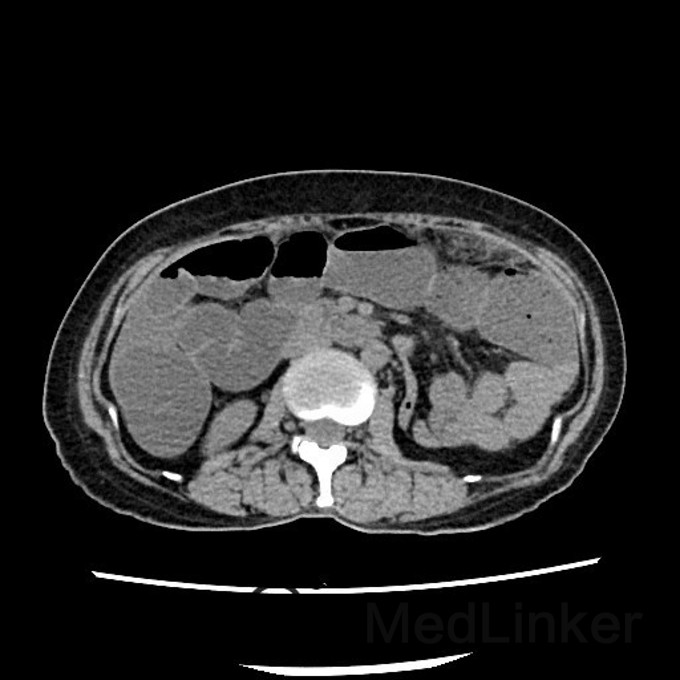

问题:患者女,50岁,因腹胀而就诊,遂行胸腹CT,提示:腹部大网膜、小网膜区脂肪间隙模糊,腹膜增厚,可见片絮状、小结节状软组织密度影,增强扫描见轻度强化。考虑转移癌可能性大。后行大网膜活检,病理结果提示:低分化转移癌。但全身PET/CT未见原发灶,此种情况下,常考虑原发灶在那些部位,以及进一步做什么检查?